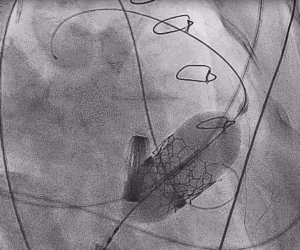

手术过程

3.经股静脉入路送入16F E-sheath可扩张导管鞘,随后送入SAPIEN 3球扩瓣1输送系统,由于肺动脉入路朝上走,无需调弯,顺利跨瓣,将SAPIEN 3球扩瓣送入预定位置。精准定位后,以160次/分快速起搏,并保证1:1完全夺获,缓慢释放瓣膜。术后超声检查结果显示即刻跨瓣压差从术前9mmHg降至3mmHg,顺利完成瓣膜释放,回撤导管、导丝。